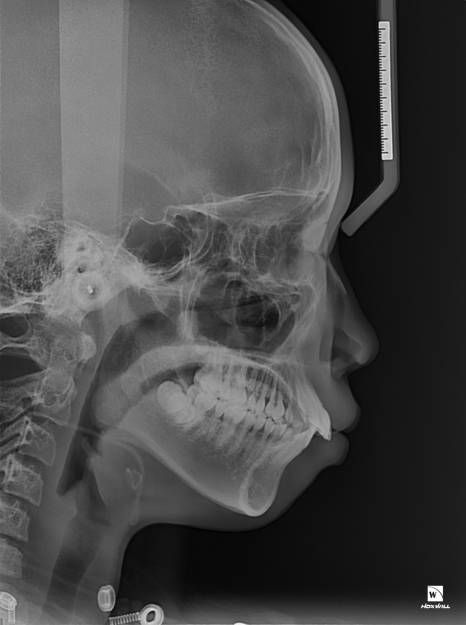

먼저 사례자분이 돌출입처럼 보였던

원인을 자세히 파악하기 위해

구강 내부를 3D CT와 3D 스캐너로

정밀하게 촬영을 거쳤는데요.

부정교합으로 인해 치아가 맞물리지 않는 상태

사례자분의 경우 상악의 앞니가

심하게 앞으로 돌출된 형태를 띠고

있었으며 상, 하악의 치아가 거의

맞물리지 않을 정도로 심각한

부정교합이 있는 상태였습니다.